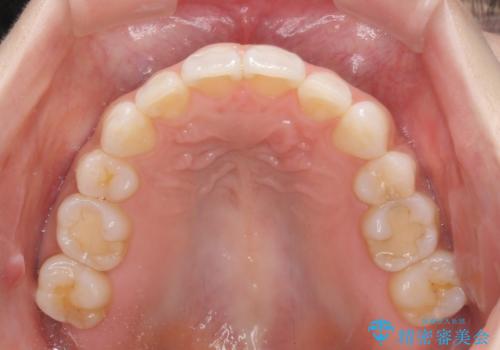

矯正治療の後戻り インビザラインによる再矯正治療

- 以前ワイヤー装置にて行った抜歯矯正の後戻りを気にして来院された患者様です。

前歯のデコボコにより、やや口元が突出した印象となっていたため、口元も引っ込めることとしました。

上下顎前歯に積極的にIPR(歯と歯の間を削る)を行い、インビザラインを用いて治療していくこととしました。

デコボコが解消されるのはもちろんのこと、突出感のあった前歯を引っ込めることができ、患者様には大変満足していただきました。